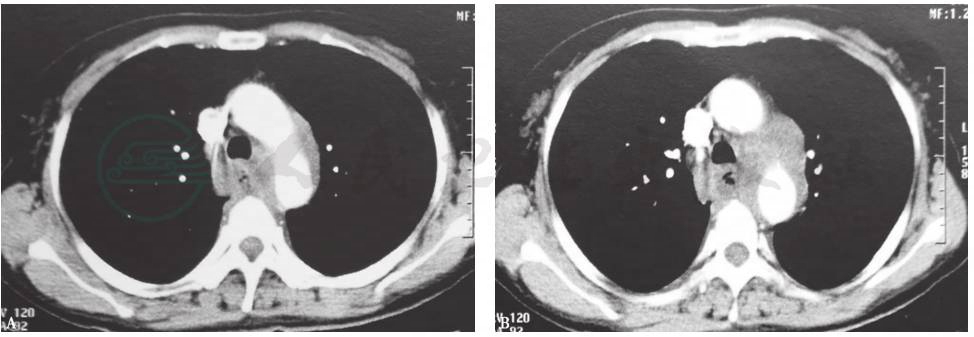

胸部CT:双肺未见肿块、结节以及斑片样、纤维条索样阴影,左主支气管狭窄(图1);增强CT可见纵隔淋巴结肿大,以左侧主动脉弓下方明显(图2)。

图1 胸部CT表现

图2 胸部增强CT表现

4.胸部CT提示,双肺未见明显病变,纵隔多发淋巴结肿大,左主支气管狭窄。